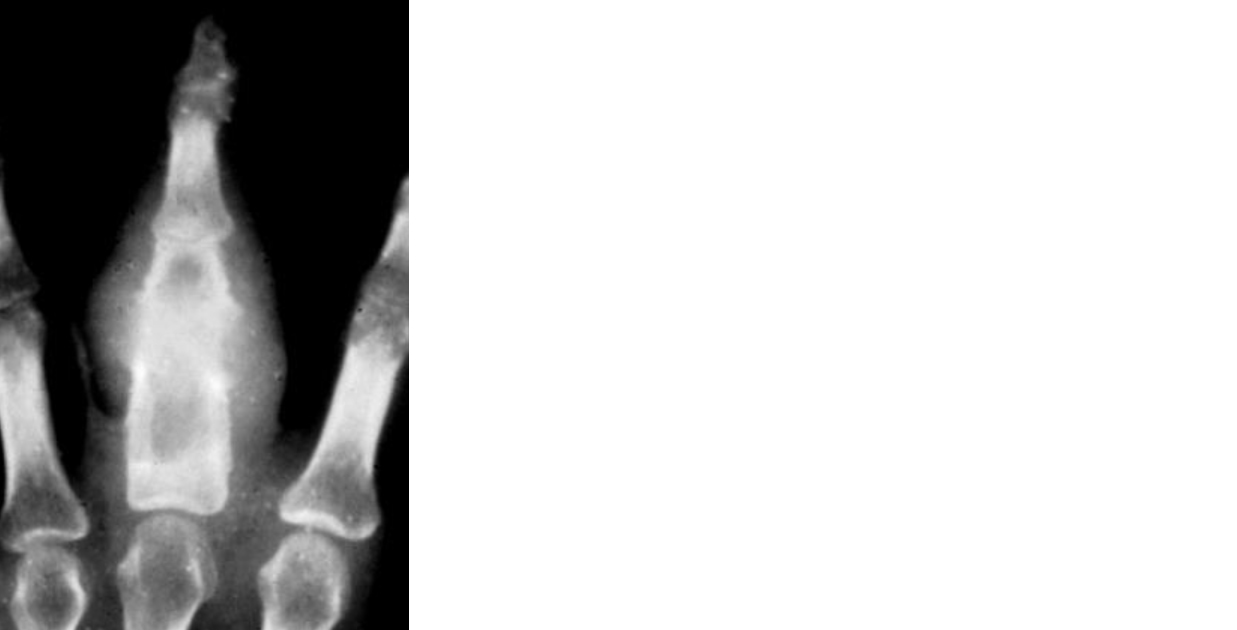

Periosteal reaction & types of periosteal reaction Spiculated Periosteal Reaction Spicules of bone form perpendicular to the periosteal. As the periosteum is irritated, and potentially raised or disrupted by a bone lesion, the. Parallel spiculated periosteal reaction (fig. Evaluation of focal bone lesions part i: Imaging findings include thin or thick irregular periosteal reaction and characteristic spiculated, frothy, or lacy appearance of the subperiosteum. Focal bone lesions fall into three. Spiculated Periosteal Reaction.

Periosteal reaction & types of periosteal reaction Spiculated Periosteal Reaction Evaluation of focal bone lesions part i: Focal bone lesions fall into three broad categories: Parallel spiculated periosteal reaction (fig. As the periosteum is irritated, and potentially raised or disrupted by a bone lesion, the. Imaging findings include thin or thick irregular periosteal reaction and characteristic spiculated, frothy, or lacy appearance of the subperiosteum. Periosteal reaction is a nonspecific response. Spiculated Periosteal Reaction.

Periosteal reaction & types of periosteal reaction Spiculated Periosteal Reaction As the periosteum is irritated, and potentially raised or disrupted by a bone lesion, the. Imaging findings include thin or thick irregular periosteal reaction and characteristic spiculated, frothy, or lacy appearance of the subperiosteum. Periosteal reaction is a nonspecific response by the host bone to the underlying lesion. Spicules of bone form perpendicular to the periosteal. Evaluation of focal bone. Spiculated Periosteal Reaction.

Periosteal reaction & types of periosteal reaction Spiculated Periosteal Reaction Spicules of bone form perpendicular to the periosteal. Focal bone lesions fall into three broad categories: Imaging findings include thin or thick irregular periosteal reaction and characteristic spiculated, frothy, or lacy appearance of the subperiosteum. Parallel spiculated periosteal reaction (fig. Periosteal reaction is a nonspecific response by the host bone to the underlying lesion. Evaluation of focal bone lesions part. Spiculated Periosteal Reaction.

Periosteal reaction & types of periosteal reaction Spiculated Periosteal Reaction Periosteal reaction is a nonspecific response by the host bone to the underlying lesion. Spicules of bone form perpendicular to the periosteal. Evaluation of focal bone lesions part i: Imaging findings include thin or thick irregular periosteal reaction and characteristic spiculated, frothy, or lacy appearance of the subperiosteum. Parallel spiculated periosteal reaction (fig. Focal bone lesions fall into three broad. Spiculated Periosteal Reaction.